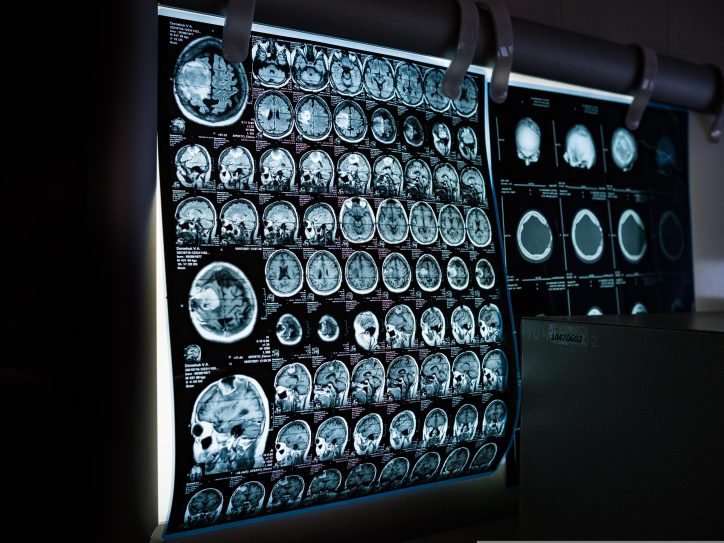

Mozak je najsloženiji organ ljudskog tela i menja se tokom celog života. Studija Univerziteta Kembridž pokazuje da ključne promene kod većine ljudi počinju u isto vreme: sa oko devet, 32, 66, i 83 godine